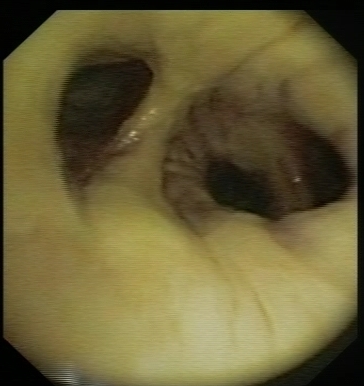

Extensive post anastomotic fibrin deposition: 1month after transplantation

Extensive post anastomotic fibrin deposition in the truncus intermedius